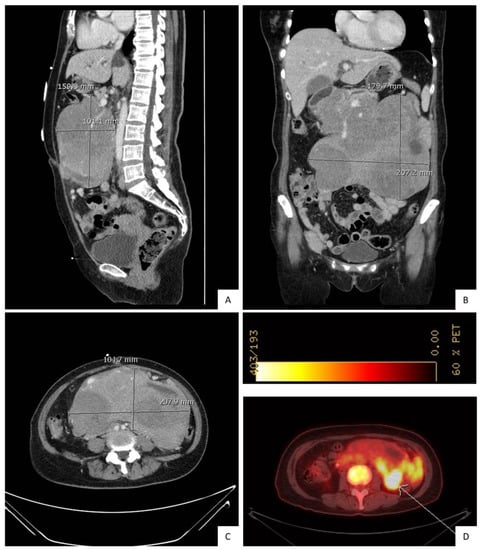

2. Case Presentation